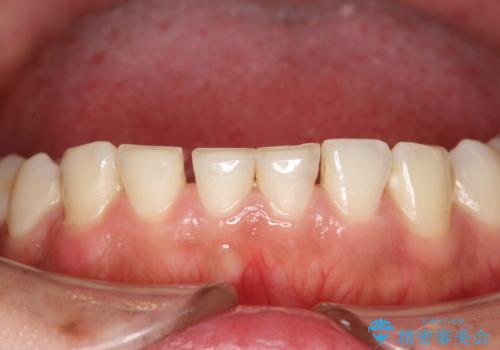

終了時

かなり久しぶりの歯科医院との事で、全体的に古くからの歯垢・歯石が多く付着していたため、自費クリーニング(PMTC)60分コース・歯周ポケット検査(保険適応)を行いました。

磨き残しが放置されると、そこで病原菌が繁殖し始めます。よって歯肉に炎症が生じ、歯周病の原因になることがあります。

定期的に、歯周病検査や専門的なクリーニングをすることで、早期発見につながります。